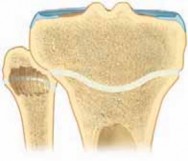

3. The curette is then swept cephalad and caudad in the physis to ablate the peripheral third of the physis, leaving the middle third intact (

TECH FIG 2C

).

5. Specific surgical attention is directed toward adequate ablation of the most peripheral aspect of the physeal plate (

TECH FIG 2D–F

--- A B CTECH FIG 2 • A. The curette is advanced through the incision into the hole of the femoral cortex. B. The curette is rotated and advanced to the level of the inner third of the physis. C. The anticipated area of ablation of the peripheral third of the physis (both medially and laterally). The curette is swept cephalad and caudad in the physis to ablate the peripheral third of the physis, leaving the middle third of the physis intact.

TECHNIQUES D E F GTECH FIG 2 •

D. A photograph of a specimen demonstrating the ablation of the peripheral third of the physis, leaving the middle third of the physis intact. E. A photomicrograph of the femoral physis distally demonstrating the ablation of the peripheral third of the physis, leaving the middle third intact. F. A computed tomography section through the femoral physis distally demonstrates the ablation of the peripheral third of the physis. Note the narrow space in the middle third of the physis, with the neurovascular bundle posteriorly (between the femoral condyles) and the patellofemoral joint anteriorly. G. The 3-mm incision has been closed with a single suture. The incision is covered by an adhesive strip and bandage.Epiphysiodesis of the Fibula Proximally 1. The same incision is used to perform the epiphysiodesis of the fibula as the proximal physis of the tibia laterally.